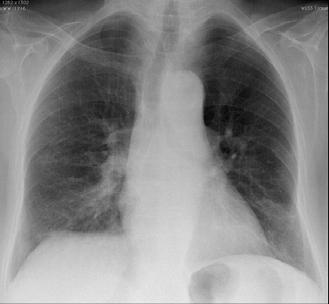

Fig 3 — CXR images from two different patients with COVID-19 showing peripheral areas of consolidation bilaterally in A and unilaterally in B (arrows). Images reproduced with permission from Covid-19 Database of the Societa Italiana di Radiologia Medica e Interventistica.